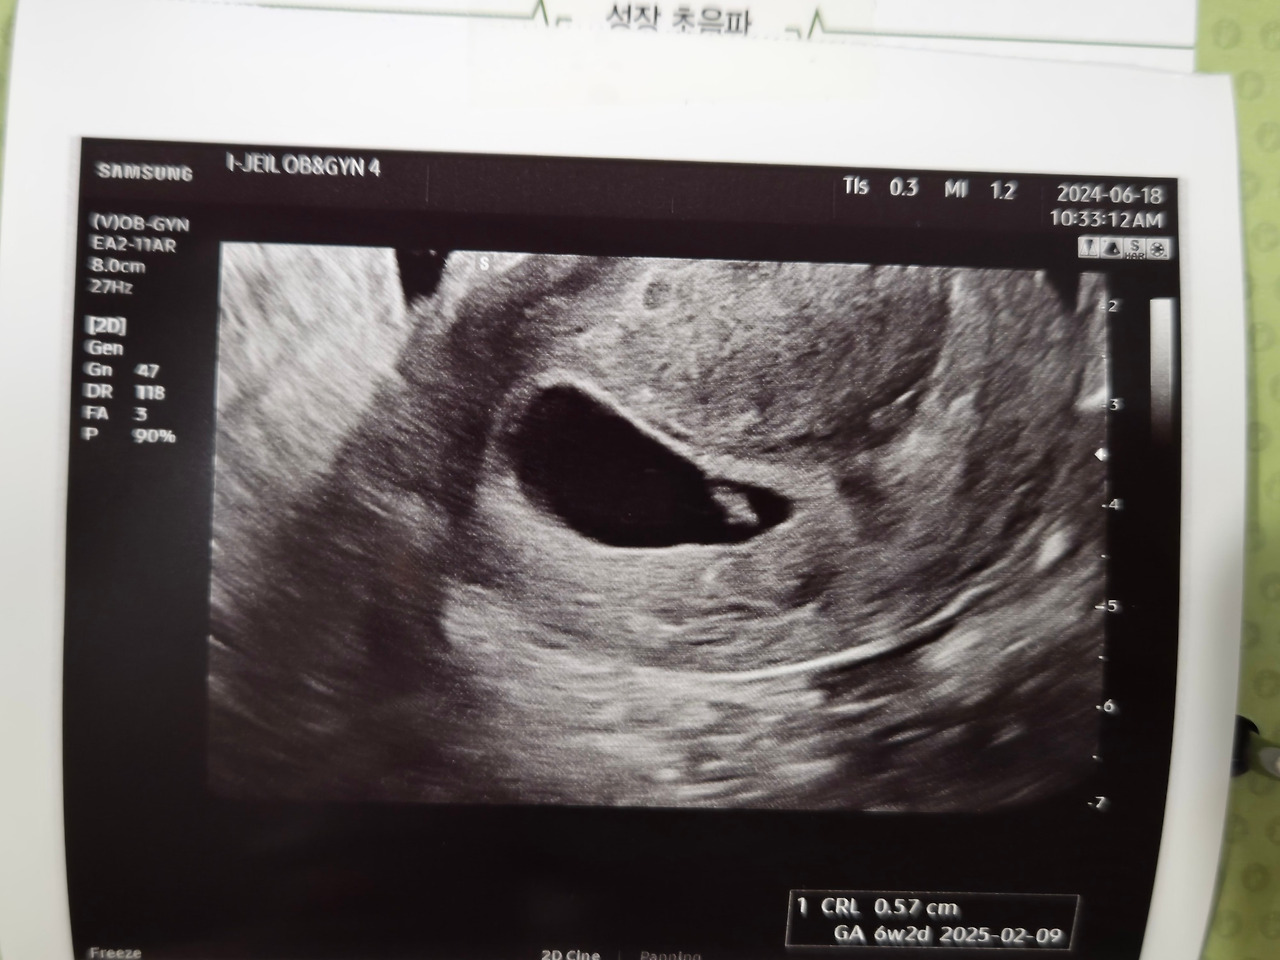

그런데 둘째 출산 후 9개월 뒤 우리에게 셋째가 찾아왔다. 아무도 모르게 와서 뱃속에 예쁘게 집을 짓고 혼자서 무럭무럭 커가고 있었다.

셋째의 등장은 아무도 예상치 못 했다. 생리일이 늦어지고 소화가 잘 안 돼 혹시나 해서 한 임신테스트기에서 본 선명한 두 줄, 자연임신으로 찾아온 셋째는 우리 가족에게 당황스러움과 놀람, 즐거움 그리고 기쁨을 함께 줬다. 그렇게 찾아온 우리 집 5호는 깜짝 선물처럼 왔다고 해서 태명이 '깜짝이'가 됐다.